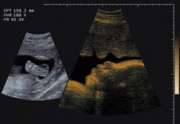

17 haftalık gebelik

Bebeğin ciltaltı yağ depoları bu gebelik haftasından itibaren hızla artmaya başlar. Bebek ve plasenta bu haftada yaklaşık aynı boyutlardadır. Ufacık kalp günde 30 litre kan pompalar. Bebeğinizin emme, yutma ve göz kırpma refleksleri de bu gebelik haftalarında ortaya çıkar.

Bu haftanın sonunda bebeğinizin ağırlığı yaklaşık 150 gram olacaktır.

Yandaki resimde ilk görüntü 17. gebelik haftasında bir bebeğin ayağını, ikinci görüntü ise yüz profilini belirgin olarak göstermektedir.